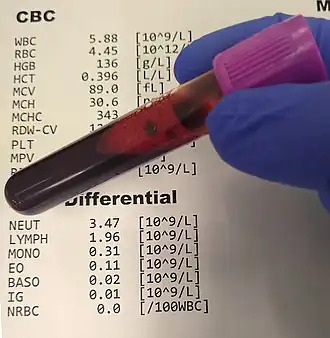

There are no laboratory or imaging tools available to diagnose PPP, though a work-up of different laboratory analyses and imaging of the brain may be conducted to ensure other potential confounding diagnoses (e.g., vascular disorders, infective delirium, etc.) are not the cause of the patient's presentation (see Differential, Other non-organic postpartum psychoses, and Organic postpartum psychoses).[6] These may include, but are not limited to, a complete blood count, comprehensive metabolic panel, urinalysis and urine drug screen, and tests for thyroid functioning; further workup in the setting of classically neurological symptoms (such as delirium-like confusion) may include magnetic resonance imaging (MRI), a test of cerebrospinal fluid (CSF), or electroencephalogram (EEG).[6]